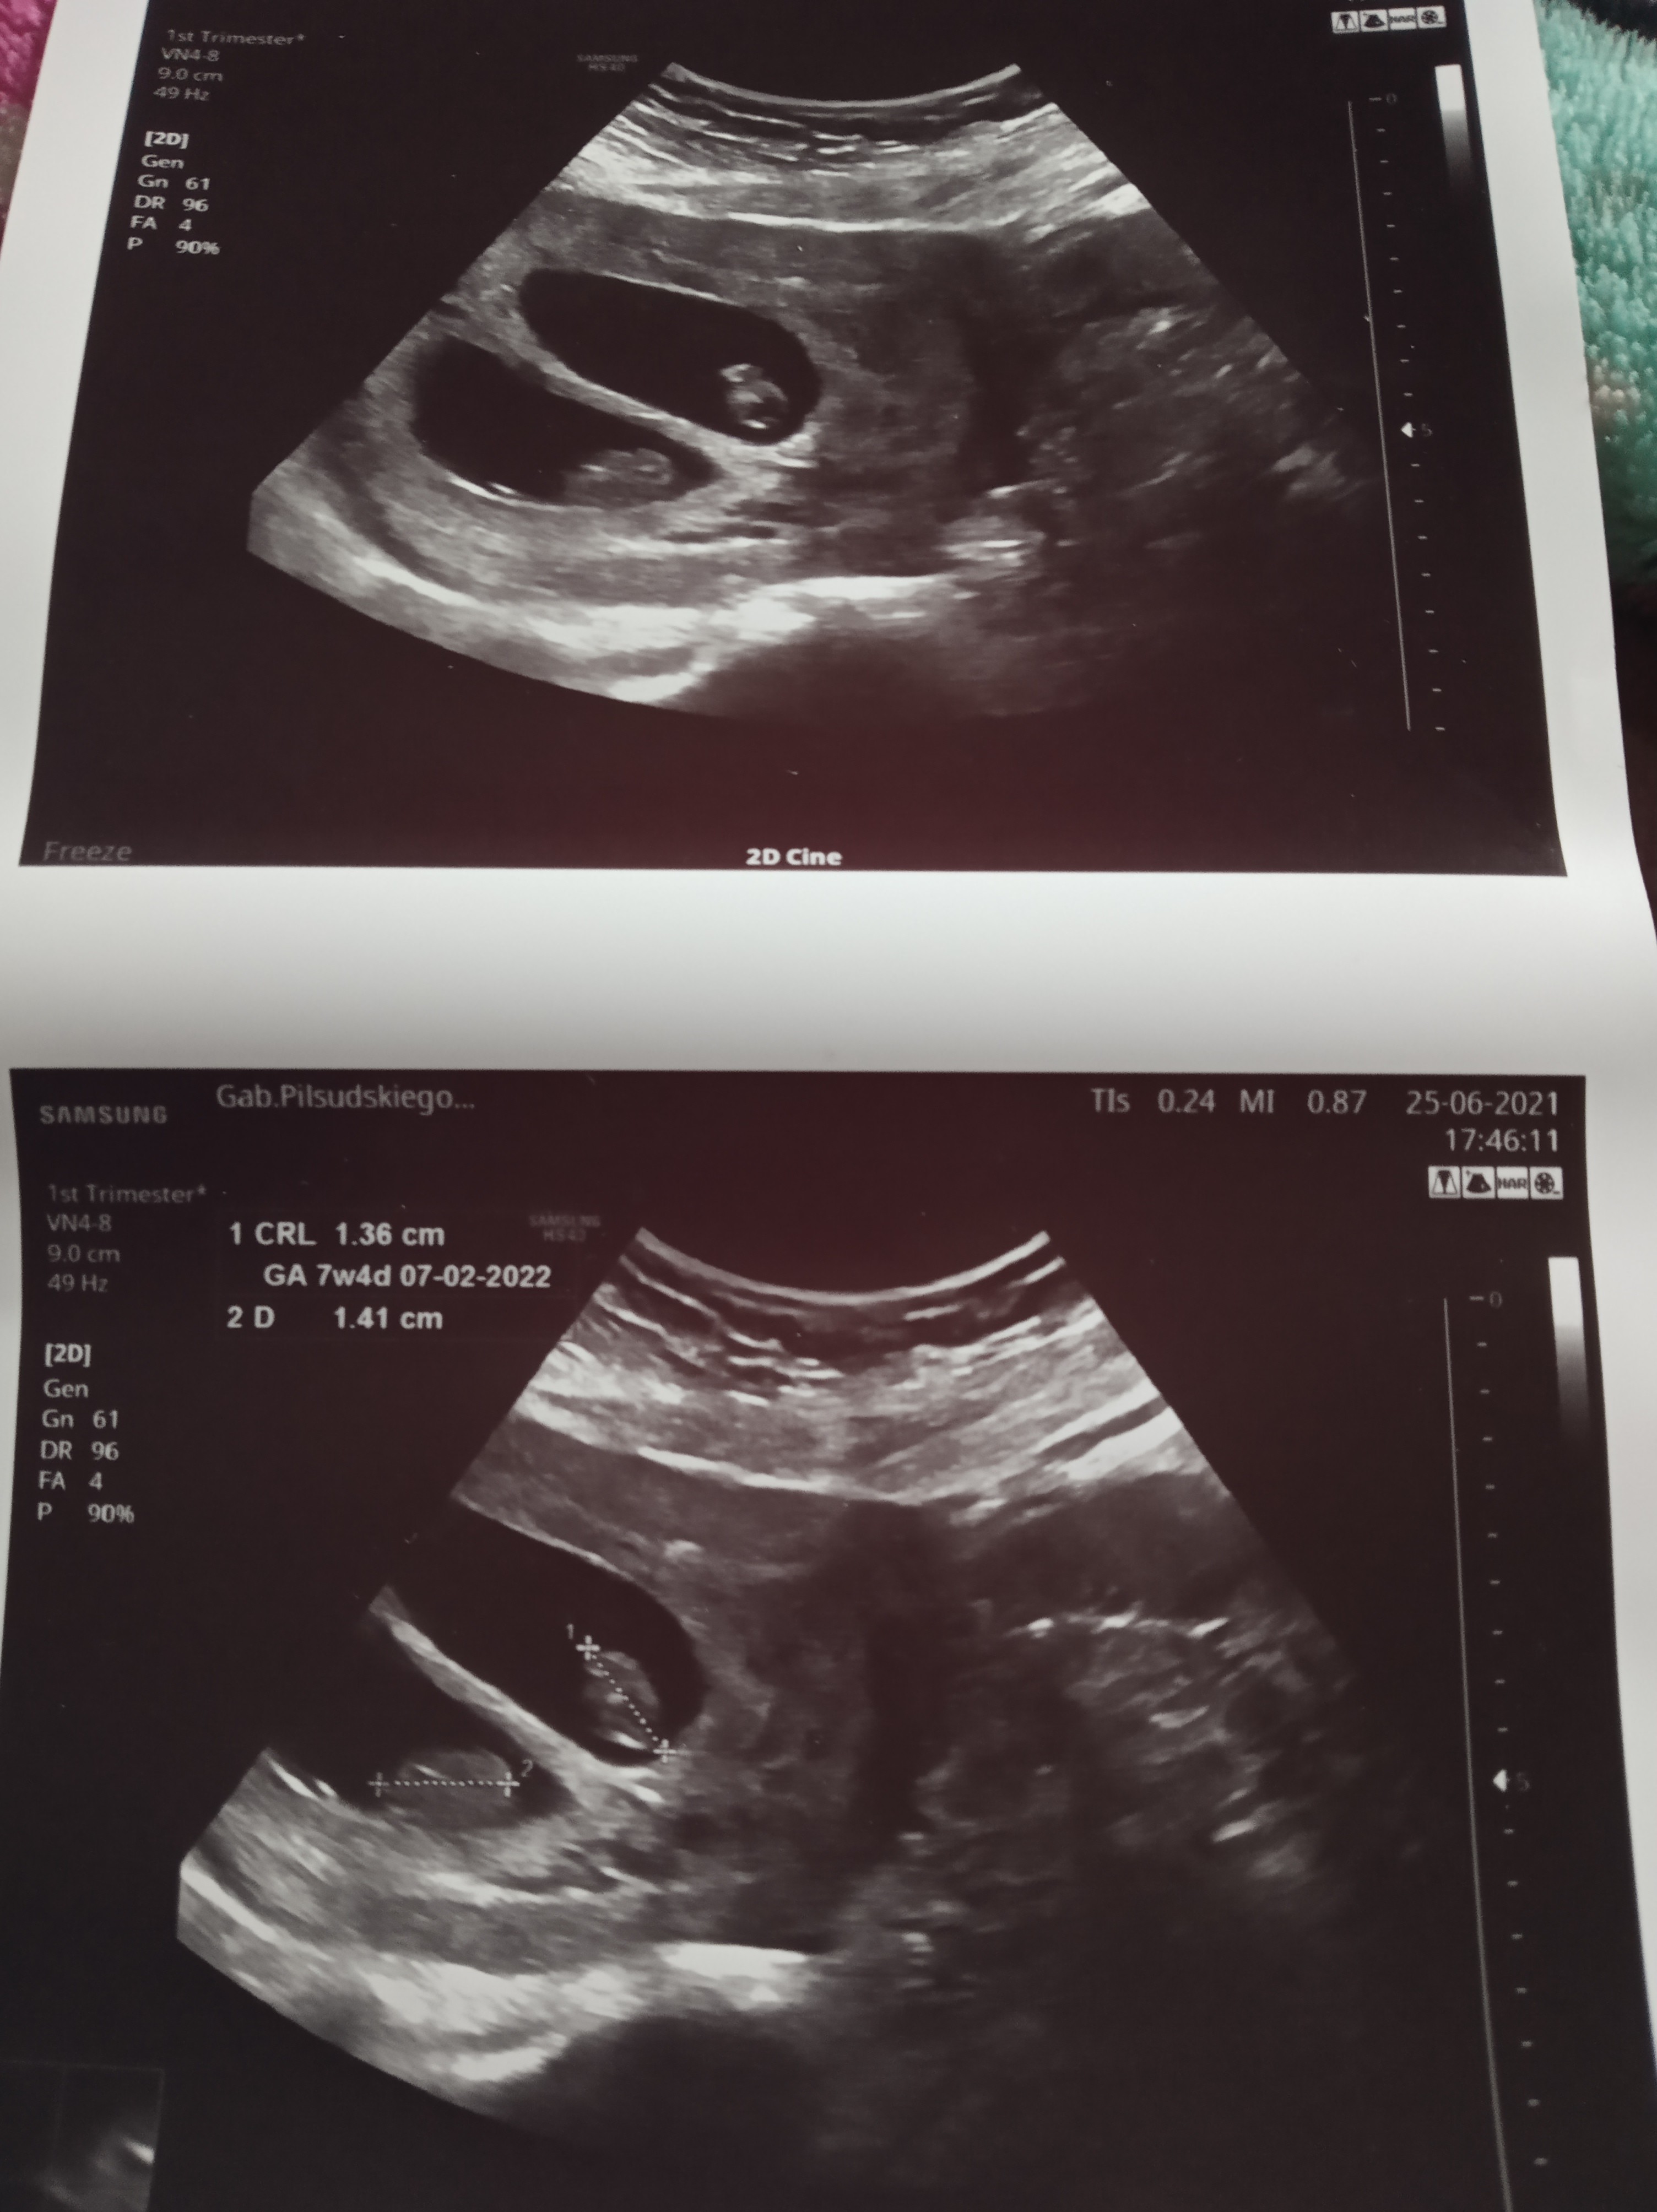

Hej! U mnie sytuacja ma się tak że według USG 7tydz plius 5 dni a według @ powinno być już koło 9tyg więc coś się musiało poprzesuwać....według lekarza wszystko ok tylko zaś był problem z USG nawet na lepszym sprzęcie widoczność na USG dopochwowym bardzo słaba prawdopodobnie przez zrosty po CC i też słabo było wychwycić tętno ale mój gin twierdzi że widzi ruch zarodków i że wykrylo przepływ krwi więc serduszka też powinny być na miejscach tylko tak jak mi to powiedział to ciąża młodsza drugi fakt bliźniaki i za dwa tygodnie kolejna wizyta i żebym była spokojna jak to on to stwierdził ciąża się trzyma może już pani się ujawnić he ( apropo moja mama położna pracuje z tym lekarzem w szpitalu) odnośnie tego ujawniania się😂

• IMG_20210625_190154.jpg

IMG_20210625_190154.jpg

943,1 KB · Wyświetleń: 137